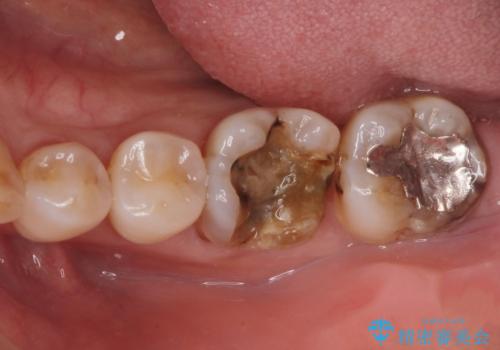

銀歯が取れた。

- 奥歯の銀の詰め物が取れたとの事で来院。

詰め物の下に虫歯ができて銀歯が取れてしまった事が予想されます。

白い詰め物でやり直しをしても歯質が薄くなり割れてしまうリスクがあるために、

割れるリスクの少ないジルコニアクラウンにて治療しました。